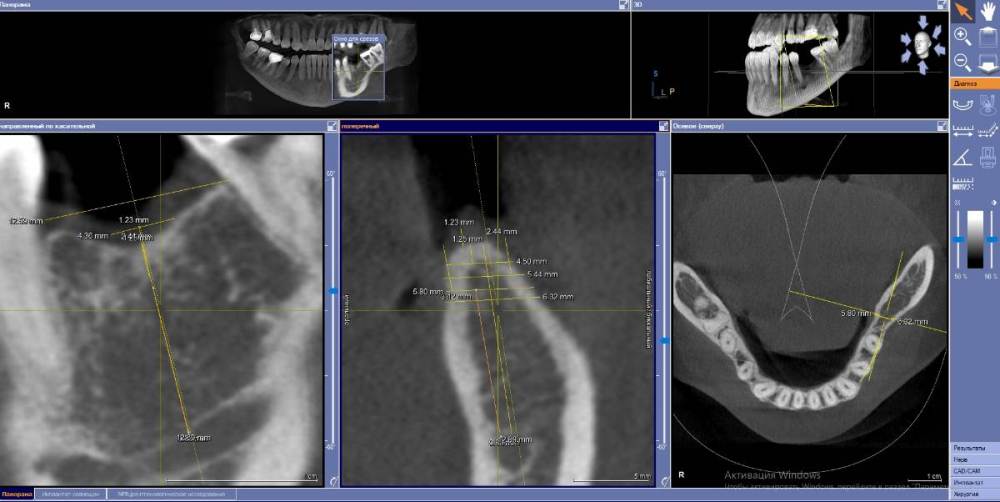

Fin Опубликовано 28 июня, 2021 Поделиться Опубликовано 28 июня, 2021 (изменено) Коллеги как бы Вы решили данную ситуацию? Давно хочу начать ставить поставить анкилос. Кто ставит как Вам клин ситуация для 3.5Х8 с заглублением в 3 мм? Пока склоняюсь к импланту диаметорм 4,5 заглубление (2 мм) и небольшой НКР спейсер+титановая сетка) потом работа с десной. Или все же поставить 4 на 8,5 +ССТ с заглублением 2,5 мм без НКР. Навигац шаблон во всех вариантах. Изменено 28 июня, 2021 пользователем Fin Ссылка на комментарий

Fin Опубликовано 28 июля, 2021 Автор Поделиться Опубликовано 28 июля, 2021 Подниму тему, немного пропал. Был в отпуске без интернета, а потом отходил от отпуска пару недель. 07.07.2021 в 23:53, АнтонТЛТ сказал: Я сотни 4.0 в моляры ставил и всё было хорошо, 3.5 тоже приходилось. Пока без проблем было. На оригинальной протетике переломов винта и имплантата у меня не встречалось. Что использовалось в данном случае, лучше спросить у Олега. В его клинике делалась работа в 16 году. Вы бы поставили 4ку в данном случае? 08.07.2021 в 21:26, Bier сказал: Сюда легко и 4.0 и 4.5 войдет. Надо выяснять. Но тут недозаглублен имплантат. ? Что делать, раньше так ставили. Я думаю, что в этом проблема. Лизис кости и затем перелом. В ширину 5.8 имплант 4.5. Вы имеете ввиду частично оголить вестибулярную часть импланта и поработать с десной? Ссылка на комментарий

Bier Опубликовано 30 июля, 2021 Поделиться Опубликовано 30 июля, 2021 28.07.2021 в 22:33, Fin сказал: В ширину 5.8 имплант 4.5. Вы имеете ввиду частично оголить вестибулярную часть импланта и поработать с десной? ну если ширина гребня 5.8 а диаметр препаровки ложа примерно 4.1-4.2 с чего вы взяли, что вестибулярная часть имплантата обнажится? Ссылка на комментарий

Fin Опубликовано 2 августа, 2021 Автор Поделиться Опубликовано 2 августа, 2021 (изменено) 30.07.2021 в 22:17, Bier сказал: ну если ширина гребня 5.8 а диаметр препаровки ложа примерно 4.1-4.2 с чего вы взяли, что вестибулярная часть имплантата обнажится? Благодарю за ответ. Все верно. Но если брать информацию того же Томаса Линчкевикуса он советует что бы минимум был 1 мм кости вокруг. Следовательно делаем 1 мм с язычной поверхности то с щечной поверхности будет около 0,3(грубо говоря нет). Изменено 2 августа, 2021 пользователем Fin Ссылка на комментарий